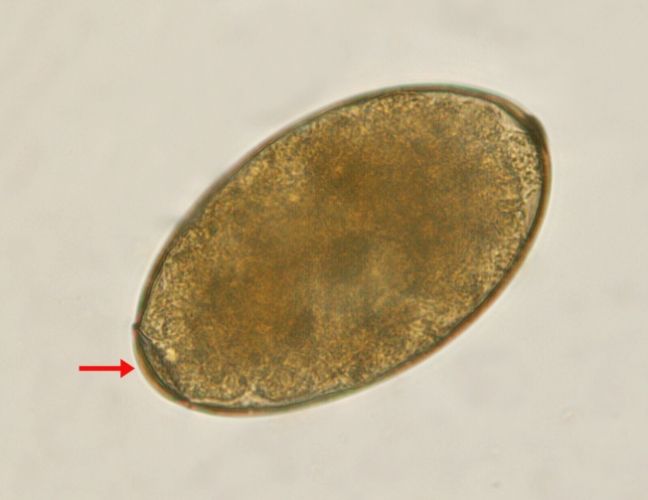

中華肝吸蟲蟲卵通常長約26-30微米,寬約15-17微米。這尺寸比很多常見蟲卵小,比如蛔蟲卵就大得多。形狀是橢圓形或卵圓形,一端有個明顯的小蓋子(operculum),另一端可能有個小突起。但說實話,蓋子有時不太明顯,得調好顯微鏡焦距。

顏色與結構:細節決定成敗

蟲卵的顏色通常是淡黃褐色或棕色,外殼光滑。在顯微鏡下,光線調整好的話,能看到內部結構——未成熟的蟲卵內含卵細胞,成熟後有毛蚴。但老實說,顏色受檢體處理影響,比如糞便的酸鹼度可能讓顏色變深。

結構上,那個小蓋子是關鍵特徵,蓋子周圍有時有縫隙,孵化時毛蚴從這裡出來。但蓋子容易脫落,檢體處理不當的話,可能誤判。世界衛生組織的寄生蟲指南就強調,診斷時要多點取樣,避免漏看。你可以參考WHO的相關頁面(寄生蟲疾病概述),了解更多全球標準。

說到這裡,我覺得中華肝吸蟲蟲卵特徵最麻煩的是變異性。同樣是感染,不同人的蟲卵可能略差別,這點在文獻中也有提到。所以,診斷不能只靠單一特徵,要綜合大小、形狀、蓋子一起看。